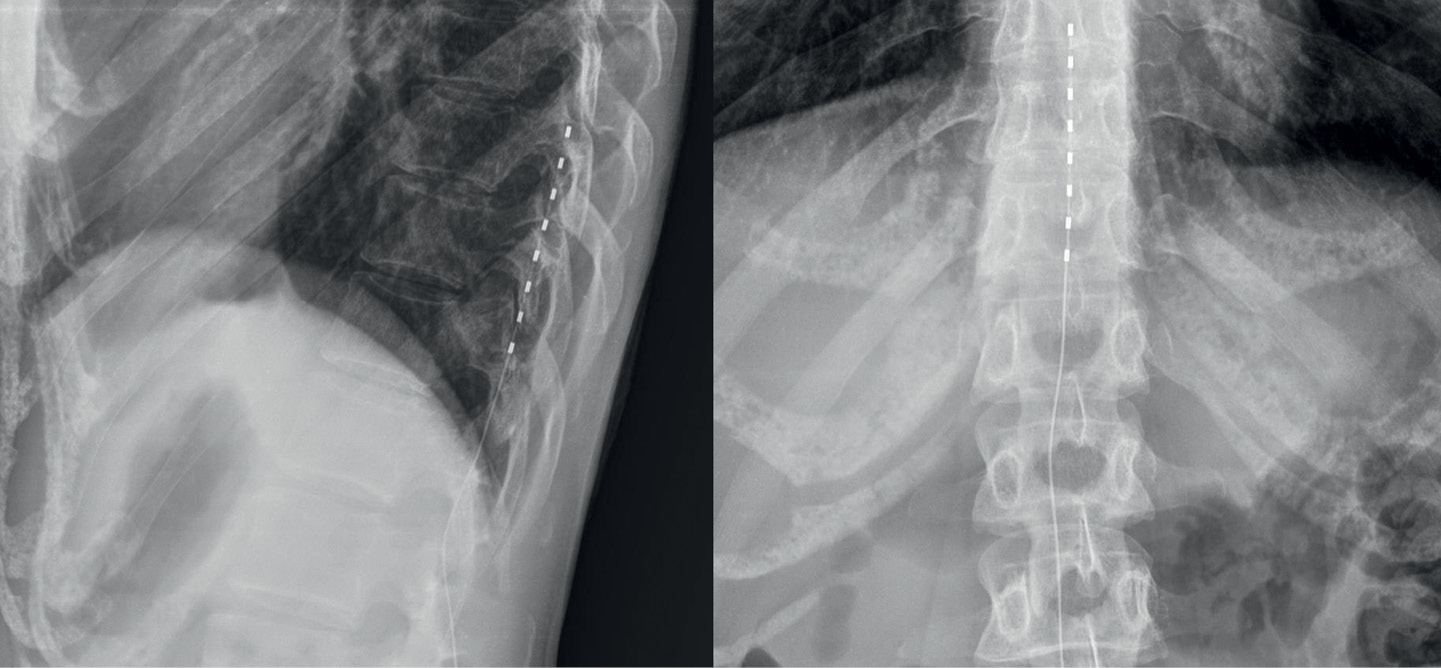

Patient S., a 32-year-old female, underwent surgical removal of a subcutaneous lipoma located on the dorsolateral surface of the left foot posterior to the lateral malleolus. In the early postoperative period, she developed a severe burning pain syndrome radiating along the lateral foot surface, accompanied by paresthesias and hypesthesia of the toes. Pain intensity reached 8 points on the visual analog scale (VAS). Neurological examination and instrumental diagnostics confirmed iatrogenic injury to the sural nerve (n. suralis) in the surgical access area. Sequential attempts at surgical management (marginal neurectomy) and conservative therapy (gabapentin 900 mg/day, duloxetine 60 mg/day, venlafaxine 150 mg/day) proved ineffective, showing only short-term analgesic effects with pain recurrence before subsequent dosing. In 2022, the patient underwent implantation of a chronic spinal cord stimulation (SCS) system at Th10-Th12 levels (Fig. 1). Stimulation-induced paresthesias covered 80% of the pain area and reduced pain intensity by 30%.

Fig. 1. Radiographic image of the implanted electrode in the posterior epidural space at the T10–T12 vertebral levels.